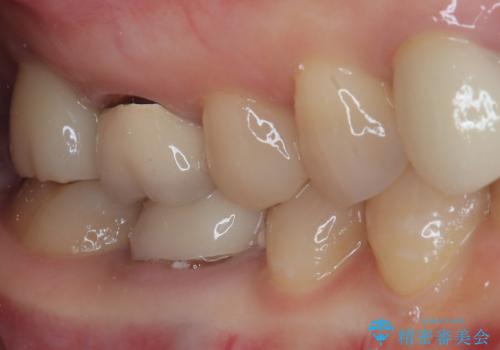

残念ながら歯冠から歯根に向かって破折が認められたため、患者様了解のもと、抜歯してインプラントの即時埋入を行いました。

インプラントと骨の安定程度を測定したところ、十分な数値が得られたため、速やかに仮歯を装着して咬合回復をさせることができました。

抜歯を含めた外科処置を1回に抑えることができ、あっという間に治療を終えることができました。